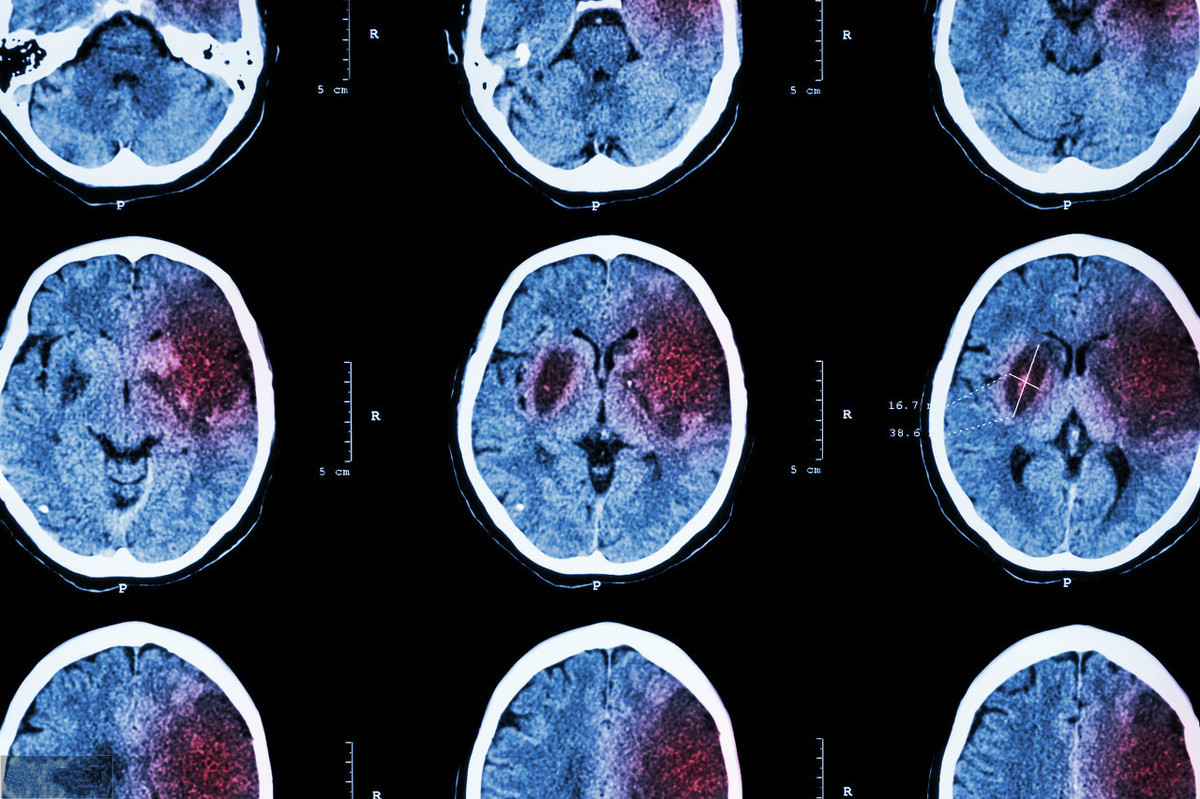

現(xiàn)實生活之中,腦出血是一種比較常見的疾病,也是一種危害性巨大的疾病,一旦病情發(fā)作,就會導致患者的身體健康遭受到致命的打擊,務必要做好相關的護理工作。那么腦出血怎么辦?

早期要立即通過頭部影像學的方法進行檢查確診,如果情況危急,需要盡早考慮通過開顱手術的方法進行治療,以免危及生命。后期在病情穩(wěn)定之后,由于會存在有腦組織的損傷,所以需要考慮通過高壓氧,配合營養(yǎng)腦神經(jīng)的藥物,促進恢復?;颊叱霈F(xiàn)腦出血,應該通過以下手段進行治療: